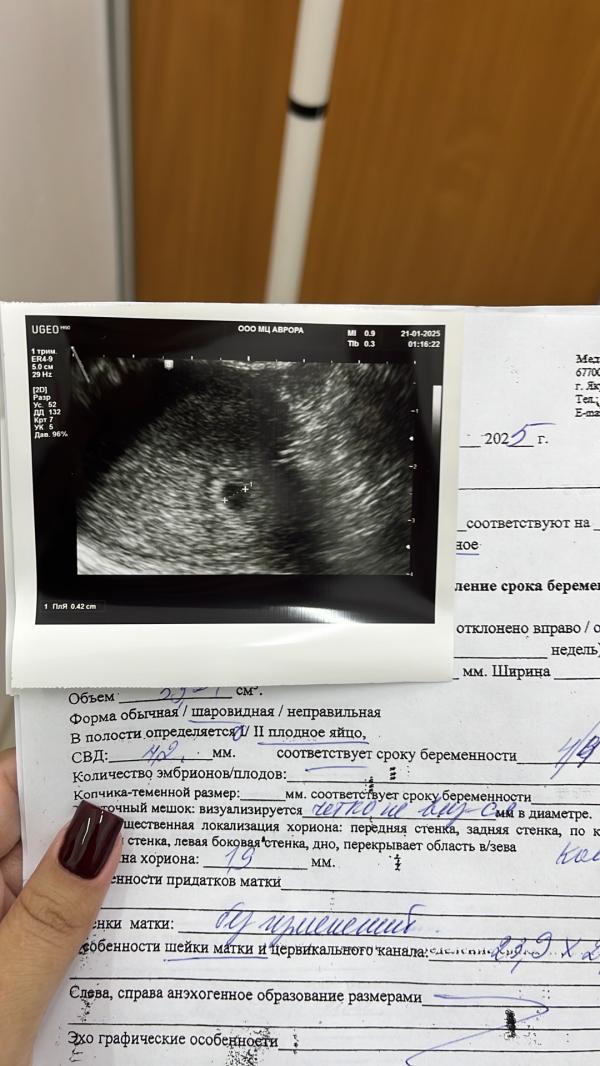

20.01 ессе да кып кыра ди кини🥰 пока только плодное яйцо, цикл уьун буолан овуляция хойутаан буолбут, еще контроль через 2 недели диэбиттэрэ, надеюсь барыта этэннэ буолар ини 🥺🙏🏼

по узи срок 4 недели 4 дня